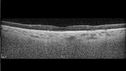

82 year old man with hemorrhagic PCV in temporal macula in the left eye.

Polypiodal Choroidal Vasculopathy - Temporal Macula - Left eye330 views82 year old man with asymptomatic PCV in the left eye. Vision 20/50 OD, 20/32 OS did well with Lucentis     (0 votes)